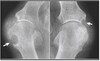

What pathology is seen here?

Congenital hip displasia

What does congenital hip displasia result from?

Results from incomplete acetabulum formation

160

What two projections are used for congenital jip displasia?

AP Bilateral Frog